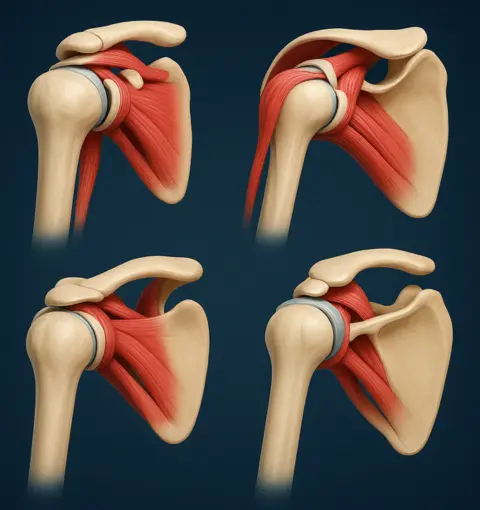

Lesão no Manguito Rotador

O manguito rotador é um conjunto de músculos e tendões essenciais para o movimento do ombro. Oferecemos tratamento especializado para lesões e rupturas.

Artroscopia de Ombro

Procedimento minimamente invasivo que permite diagnosticar e tratar problemas no ombro com pequenas incisões, recuperação mais rápida e menos dor.

O ortopedista especialista em ombro em Goiânia trata diversas condições como tendinite, bursite, lesões do manguito rotador, luxação do ombro, rompimento de tendões, artrose, capsulite adesiva (ombro congelado), fraturas e outras patologias que afetam a articulação do ombro.